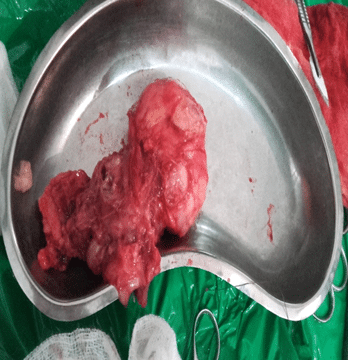

Extradigital Painless Mass of the Thigh: A Rare Presentation of Glomus Tumors

Glomus tumors (GT) are a rare benign disease that originates from the neuromyo-arterial glomus body, characterized by a triad of...Read More